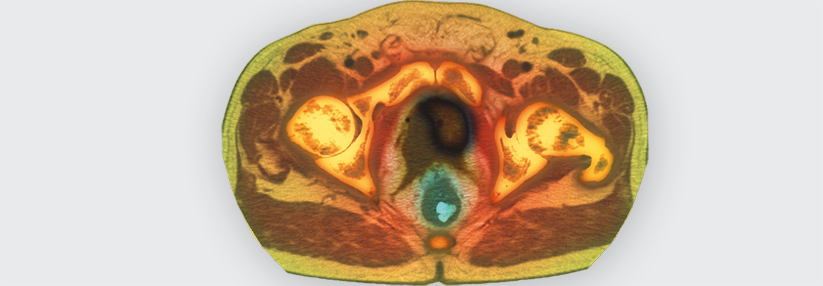

Die ärztliche Aufklärung und Empfehlung über das PSA-Screening ist auch bei Transfrauen sehr wichtig. Die ärztliche Aufklärung und Empfehlung über das PSA-Screening ist auch bei Transfrauen sehr wichtig. © angellodeco – stock.adobe.com